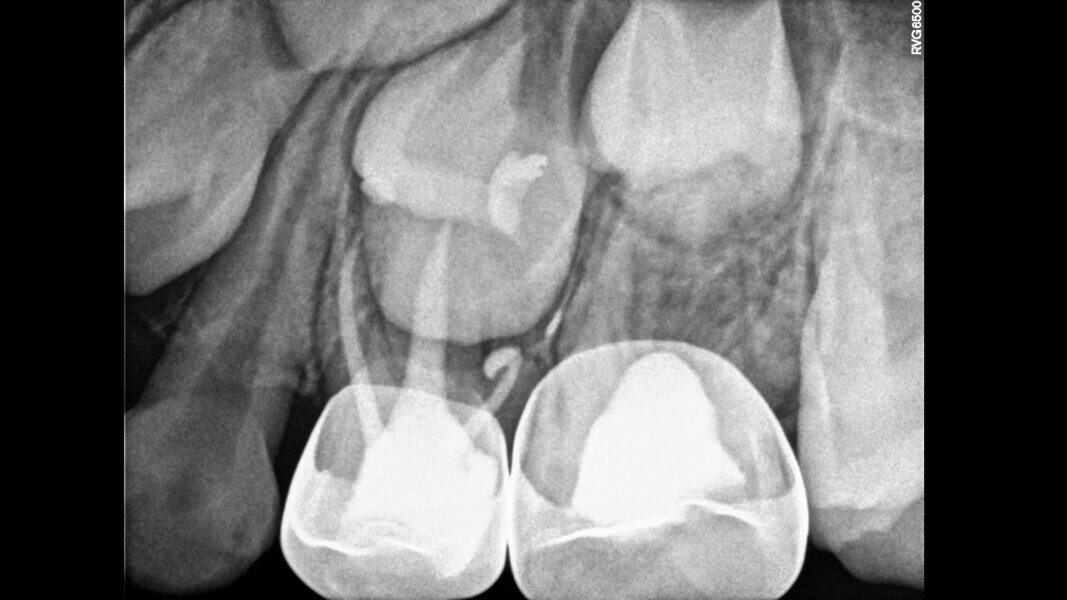

Case 4 (Figs. 14–18)

This male patient was 4 years and 6 months old and presented with constant and spontaneous pain of the mandibular left first primary molar that had lasted for several days but no facial oedema or buccal gingival swelling. Deep decay was observed but no mobility or deep probing depths. On the radiograph, the carious lesion could be seen to be compromising the pulp chamber and initial bone damage was observed in the septal area. Pulpectomy was the treatment of choice. In the removal of the carious lesion, the pulp was exposed and no bleeding was observed. Pulp necrosis was diagnosed. Two mesial and two distal canals were located, and the tooth was obturated. At a second appointment, the tooth was asymptomatic and was restored with a stainless-steel crown. At the 30-month control, the tooth presented no symptoms and a normal eruptive process was observed on the radiograph.